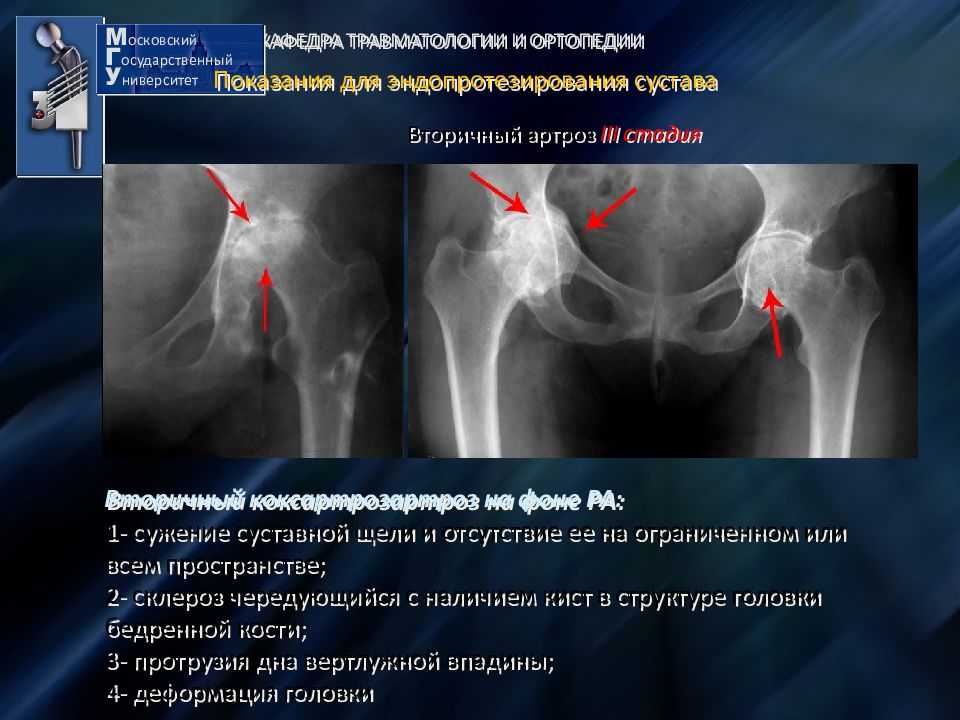

Рентгеновские снимки: Синовит тазобедренного сустава